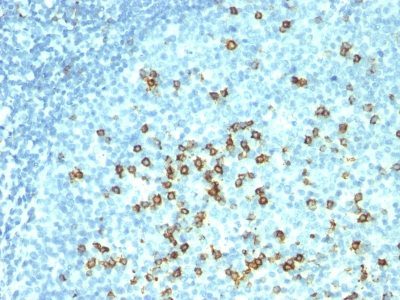

CD57 / B3GAT1 Monoclonal Mouse Antibody (NK-1 + HNK-1)

抗 CD57 标记了称为自然杀伤 (NK) 细胞的淋巴细胞亚群。滤泡中心细胞淋巴瘤通常在肿瘤滤泡内含有许多 NK 细胞。抗 CD57 还可染色神经内分泌细胞及其衍生肿瘤,包括类癌瘤和髓母细胞瘤。当与包含针对 GLUT1、CD5 和 CEA 的抗体的组合组合时,抗 CD57 还可用于将 B3 型胸腺瘤与胸腺癌区分开来。